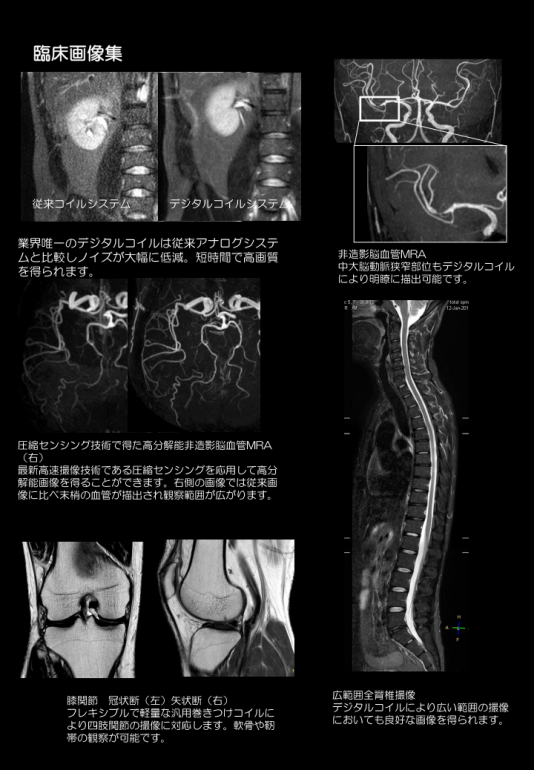

一口にMRIといってもその性能は導入されている機器によりに大きく異なります。

表向きには同じ性能を謳っていても実際に出力される画像は機器毎にかなり差があります。

画質は国産製MRIに比べて、海外製のものが綺麗な画像を出す傾向があります。

当院では画質に定評のある海外のフィリップス製MRIを導入しております。

綺麗な画像で的確な診断を行いたいという、院長の意向から導入が決まりました。

各所から様々なMRI機で経験を積んだ撮影技師を複数人呼び、当院のMRIで撮影を行ってもらったところ、

どの技師からも「画像の綺麗さは申し分ない。」とお墨付きの評価をいただいております。